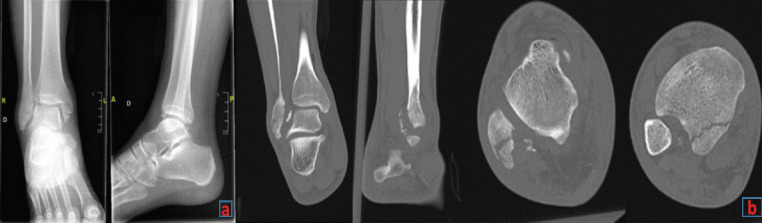

Case report: A 41-year-old male presented after a bicycle accident with a complex ankle fracture involving a transverse medial malleolus fracture, a postero-medial tibial fragment, a fibular tip fracture, and two additional posterior fibular fragments. Despite initial fracture management, including closed reduction and open fixation, the patient developed chronic pain and instability due to malreduction. Computed tomography imaging revealed instability of the fibula within the fibular notch, indicating syndesmotic instability. The surgical procedure included fibular osteotomy, temporary fixation with K-wires, syndesmotic fixation with the TightRope® system, and PITFL repair using the InternalBrace™ ligament augmentation system. Intraoperative three-dimensional imaging confirmed successful reduction and stabilization.